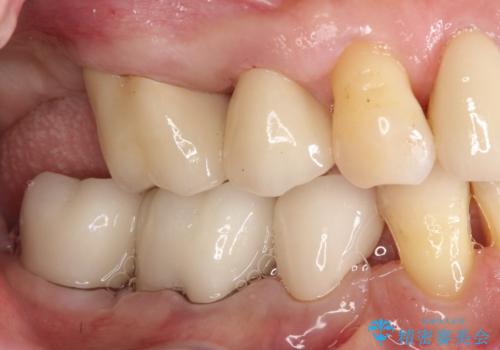

歯周病の進行した歯の抜歯。オールセラミッククラウン

最後方臼歯は根尖部まで歯周病が進行しており、抜歯を行なったのち、残存歯は歯周外科を行なったのちオールセラミッククラウンにて修復治療を行なっています。